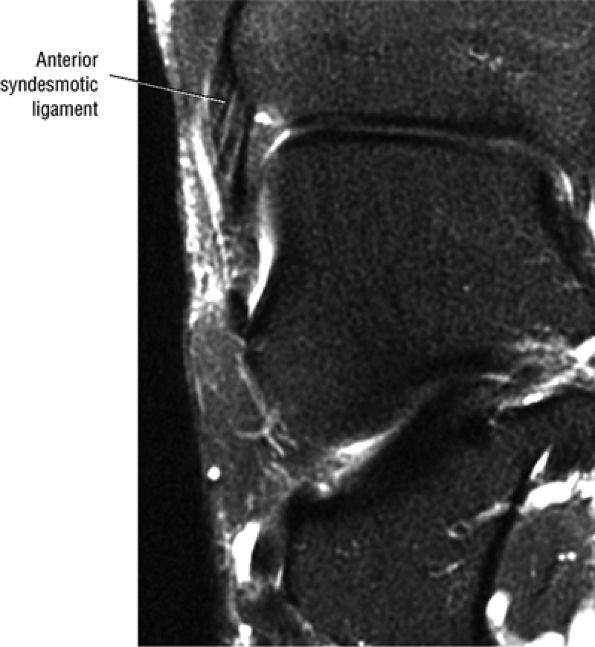

The syndesmotic ligaments consist of the anterior syndesmotic or anterior inferior tibiofibular ligament and the posterior syndesmotic or posterior inferior tibiofibular ligament, the interosseous membrane, and the transverse tibiofibular ligament.

FIGURE 5.27 ● Axial anatomy of the ankle and foot. (A) The flexor digitorum longus, flexor hallucis longus, peroneus brevis, soleus, and extensor digitorum muscles are examined at this level for strain, tears, or fatty atrophy that may suggest denervation. (B) The tibialis anterior, extensor hallucis longus, and extensor digitorum longus tendons are examined on every ankle MR examination. Extensor tendon pathology is frequently overlooked if these tendons are not included as part of the ankle checklist. (C) Tears and sprains of the anterior syndesmotic ligament are a frequent cause of persistent ankle pain following ankle sprain. The syndesmotic ligaments are thick, tough ligaments that are important ankle stabilizers, and delayed diagnosis of syndesmotic tears may result in significant degenerative arthrosis at the tibiotalar joint due to the resulting ankle instability. The syndesmotic ligaments course obliquely inferiorly from the tibia to the fibula and are not usually visualized in their entirety on a single axial image; rather, their course is followed on at least two or three successive axial images. (D) The peripheral margin of the peroneal tendons and tibialis posterior tendon should normally never extend beyond the peripheral margins of the lateral and medial malleoli, respectively. Tendon subluxation around the posterior corner of either malleolus is indicative of a tear of the overlying flexor retinaculum (medially) or peroneal retinaculum (laterally). When the retinacula are torn, the tendon is free to intermittently sublux or dislocate, leading to tendon degeneration, pain, and tendon dysfunction. (E) Suspected osteochondral lesions of the talar dome are visualized and further characterized on axial images through the top of the talar dome. (F) The peroneus brevis tendon may normally appear somewhat flattened. However, as the tendon degenerates, it becomes U-shaped and drapes around the anterior aspect of the peroneus longus and becomes impinged between the peroneus longus tendon and the lateral malleolus. With further degeneration, the peroneus brevis may split or completely rupture. (G) Evidence of anterior talofibular ligament injury is visualized on the majority of MR ankle examinations and appears as thickening, intermediate signal with ill-defined fibers, or attenuation of the ligament. This is commonly asymptomatic. (H) Because the flexor hallucis longus tendon sheath communicates with the tibiotalar joint, fluid may normally be present within the tendon sheath in proportion to the amount of fluid in the tibiotalar joint. If there is fluid within the tendon sheath out of proportion to that seen in the tibiotalar joint, tenosynovitis is most likely present. The finding of flexor hallucis longus tenosynovitis should prompt a search for an os trigonum, as impingement of the flexor hallucis longus tendon between an os trigonum and the posterior tibial plafond is a common cause for FHL tenosynovitis. (I) The calcaneofibular ligament (CFL) passes anterior and medial to the peroneal tendons. On the image at which the CFL passes directly medial to the peroneus brevis tendon, the appearance of the peroneus brevis and the CFL side by side is occasionally mistaken for a split peroneus brevis tendon. (J) Dilated posterior tibial veins within the tarsal tunnel occasionally compresses the tibial nerve. In the setting of clinical suspicion for tarsal tunnel syndrome or if there is evidence of muscle denervation on MR images, the size of the posterior tibial veins should be described. (K) The spring ligament is identified at this axial image location, extending from the anteromedial calcaneus to the posteromedial navicular. Tears of the spring ligament may result in medial instability and hindfoot valgus. (L) The posterior tibialis tendon (PTT) may normally become thickened and fan-like as it passes posterior to its navicular insertion (prior to also inserting on the cuneiforms and the base of the second through fourth metatarsals). In the absence of other findings, the thickening of the PTT at this level should not be mistaken for focal tendinosis. (M) On inferior images through the ankle, Lisfranc's ligament is occasionally included in the FOV. Lisfranc's ligament extends from the medial cuneiform to the base of the second metatarsal. If Lisfranc's ligament is included in the FOV, the status of the ligament should be described, as undiagnosed Lisfranc ligament tears can lead to debilitating midfoot arthrosis. (N) As the medial and lateral tendons turn from their vertical course to a horizontal course along the plantar aspect of the foot, the tendons may demonstrate a magic-angle artifact, causing the tendons to appear gray on short-TE images, mimicking tendinosis. Correlation with images using longer TE values is advised in such situations.